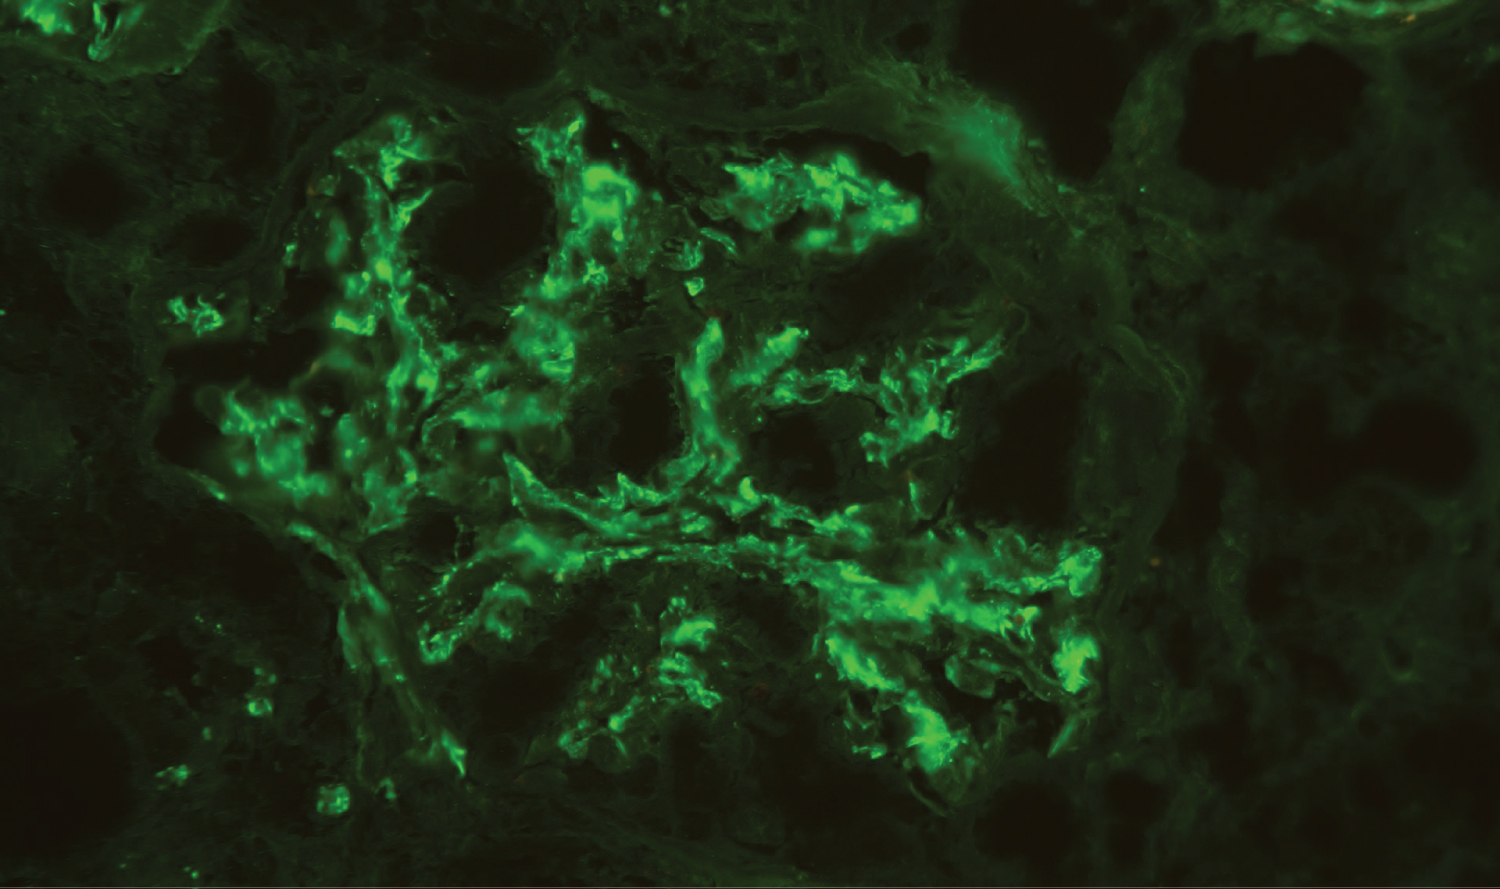

He was admitted for progressive anorexia, malaise and peripheral edema with one month of evolution. His vital signs were normal and besides bilateral peripheral edema, physical examination was unremarkable. Complementary tests revealed anemia (hemoglobin 10.7 g/dL) and acute kidney injury (AKI) (sCr 2.4 mg/dL) and the patient was transferred to the Nephrology Department for pursuing study. Additional study showed elevated erythrocyte sedimentation rate (102 mm/hour) and serum immunoglobulin (Ig) A (6,06 g/L; RV < 4.00); serum circulating immunocomplexes (89.31 RU/mL; RV < 20); mixed alkalosis and hypokalemia on arterial blood gas (pH 7.503, pCO2 26.2 mmHg, HCO3 22.9 mmHg, K 3.2 mEq/dL); urinary protein-to-creatinine ratio of 237 mg/g, urine specific gravity of 1,008 and leukoerythrocyturia on urinalysis (377/uL and 106/uL, respectively). Urinary sediment showed abundant dysmorphic erythrocytes (RBCs) and RBC casts under microscopy, with lipiduria and renal tubular epithelial cells (Figure 1). Further study, including monoclonal, polyclonal and infectious panel, was negative. Renal ultrasound excluded urinary calculi or obstruction. A kidney biopsy was performed. Under light microscopy, glomeruli revealed slight mesangial expansion and proliferation (Figure 2). The interstitial compartment showed mild mononuclear interstitial inflammatory infiltrate and fibrosis involving about 30% of the biopsy fragment (Figure 3). There was also acute tubular necrosis foci and tubular hematuria. No interstitial granulomas or crystal clefts were found. Congo red staining for amyloid was negative. Direct immunofluorescence examination of frozen renal tissue demonstrated mesangial deposits positive for IgA (++) and C3 (++) (Figure 4). These findings were consistent with interstitial nephritis due to salicylates and IgA nephropathy secondary to UC.

Figure 4: Direct immunofluorescence - Mesangial deposits of IgA (++). Deposits of C3 were also present (not showed). C1q, Kappa and Lamba were negative (not showed). View Figure 4